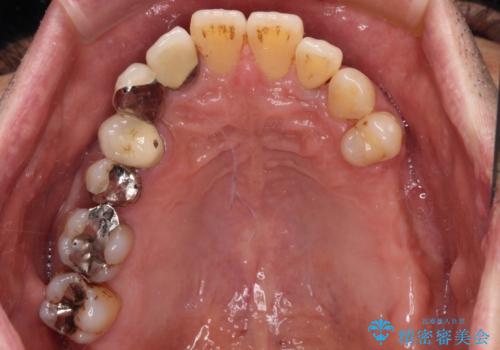

- 以前入れ歯を製作したものの、装着感が悪く使用できなかったとのことで来院された患者様です。

インプラントによる治療プランも提案しましたが、インプラントは避けたいとのご希望であったため、入れ歯による補綴治療を行うこととしました。

より適合の良い義歯とするため、セラミッククラウンなどは義歯の設計に合わせた土台の歯となるよう全て再製作をし、安定感に優れた義歯を製作することができました。